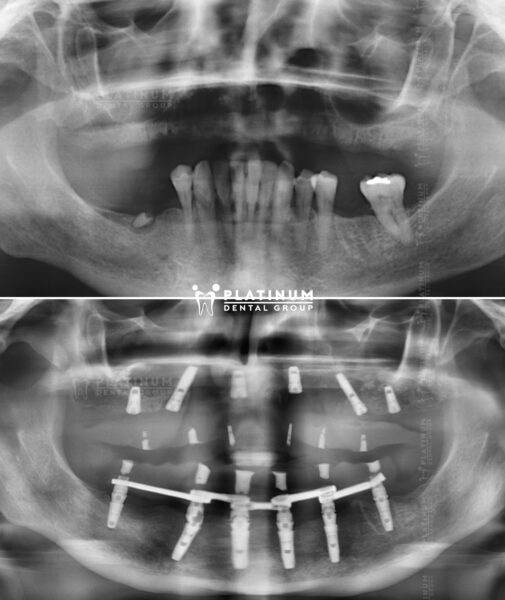

Cô Annett không tưởng tượng được hàm răng đầy đặn và thoả sức cười tươi như thế này sau khi cắm implant tại nha khoa Platinum. Một sự thay đổi đáng kinh ngạc!!!